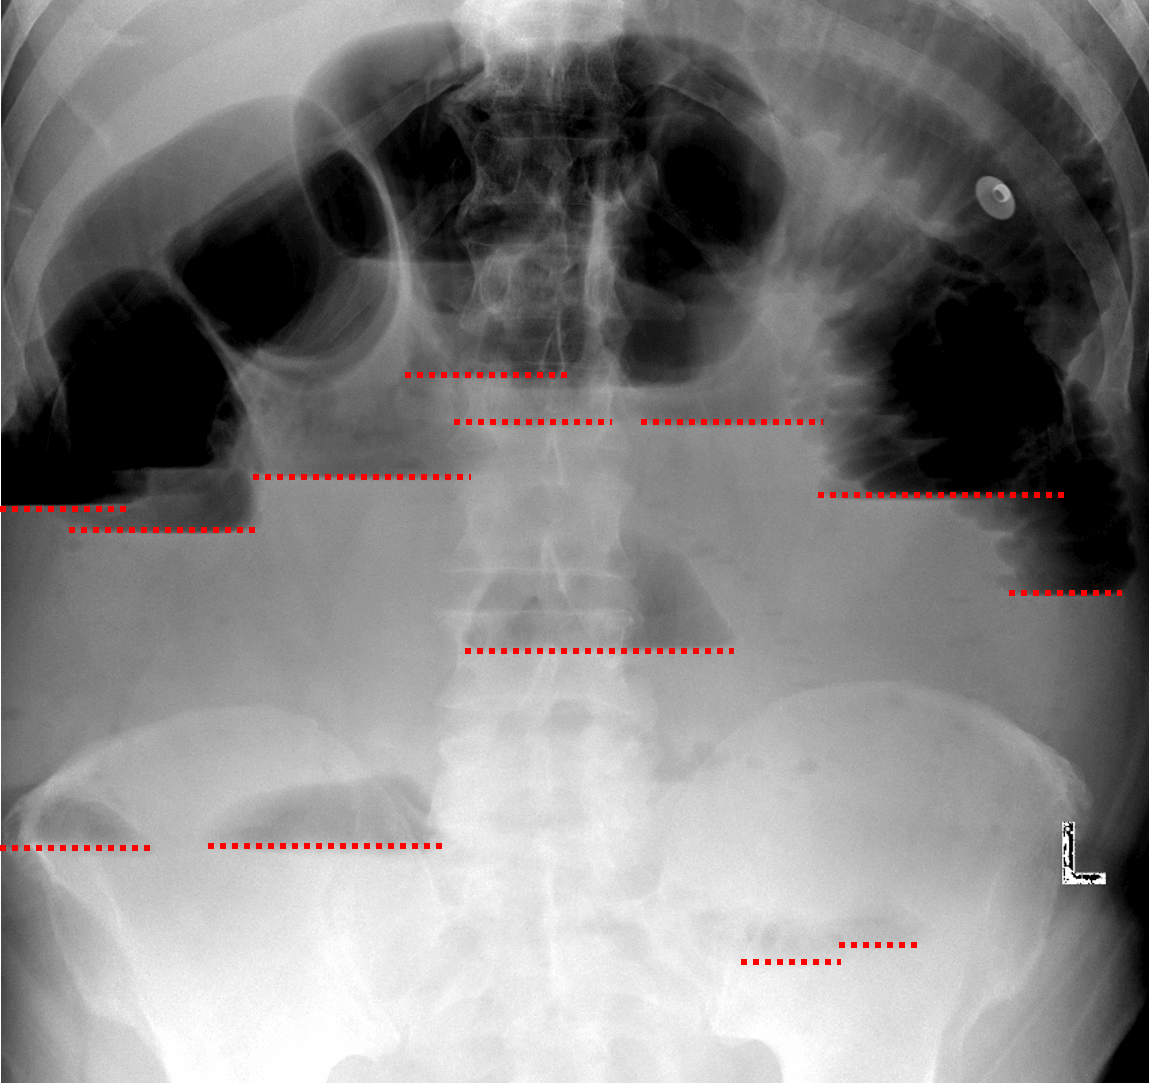

Demographics: 46 years old, Male

Indication: Diffuse abdominal pain

• Multiple dilated loops of small bowel throughout the abdomen measuring up to 5 cm in diameter with multiple air-fluid levels on upright imaging

• Paucity of colonic and rectal gas

• No evidence of pneumoperitoneum on upright images

Small bowel obstruction

Findings are concerning for high-grade distal small bowel obstruction. No evidence of pneumoperitoneum. Consider CT for further evaluation.

Small bowel obstruction. Red dotted lines highlight many air-fluid levels at different levels in the abdomen on upright imaging.